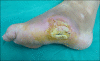

Eccrine syringofibroadenoma is a rare adnexal tumor of eccrine ductal differentiation with variable clinical features. It manifests as either a solitary or multiple papules and nodules arranged in a symmetrical or linear pattern. The anatomical distribution is wide and includes the face, trunk, extremities, and rarely the nails. Histopathological findings show anastomosing cords and strands of uniform cuboidal cells surrounded by fibrovascular stroma. Herein, we report a case of reactive eccrine syringofibroadenoma which developed on the foot of a 37-year-old woman, after self-paring of tissue and subsequent infection and ulceration.